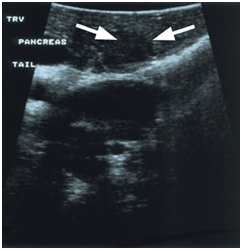

Preoperative transabdominal US

Like several abdominal disorders, transabdominal US yields the widest range of success and failure of all preoperative localization tests. It is non-invasive, free of radiation exposure, readily available, relatively inexpensive, and anatomically precise. Key major drawbacks include its extreme dependence on operator expertise and limitations based on the patient's habitus that is usually unfavorable since many insulinoma patients are overweight or obese. Overall sensitivity of this test is 27% in recent series.14–22